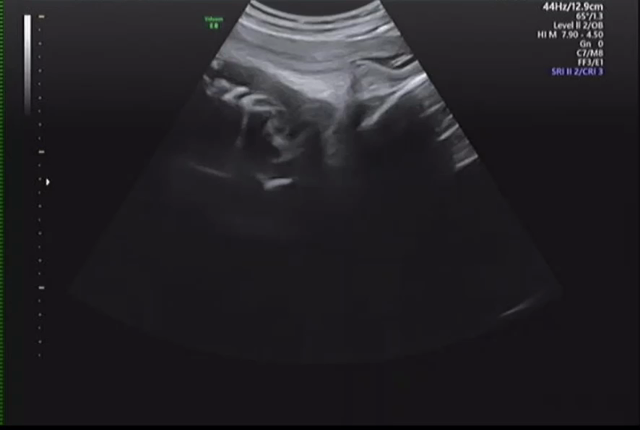

1回目の血液検査とエコー検査